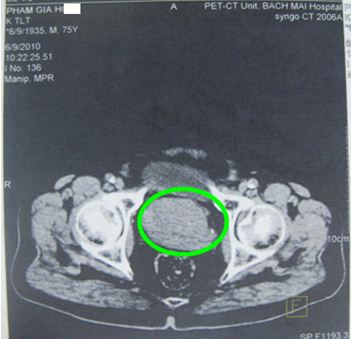

Ở Việt Nam, Mai Trọng Khoa và cộng sự lần đầu tiên thành công trong việc ứng dụng kỹ thuật PET/CT mô phỏng lập kế hoạch xạ trị điều biến liều (IMRT) cho bệnh nhân UTTTL. Ngoài ra PET/CT cũng được sử dụng để đánh giá hiệu quả điều trị cho các bệnh nhân ung thư tuyến tiền liệt (hình 2).

Hình 2. Hình ảnh CT và PET/CT trước điều trị của một bệnh nhân nam 75 tuổi được chụp tại Trung tâm Y học hạt nhân và ung bướu-Bệnh viện Bạch Mai. Bệnh nhân bị đi tiểu ra máu, tiểu khó. Mô bệnh học sau sinh thiết là: ung thư biểu mô tuyến. PSA: 145 ng/ml. Tuyến tiền liệt to: 6 x 4,9 x 5,1 cm, nhu mô không đồng nhất, tăng hấp thu FDG không đồng đều, max SUV=4,98. Có chỉ định xạ trị điều biến liều (IMRT): 6 trường chiếu, 45 segments, đạt tổng liều 74 Gy vào u.